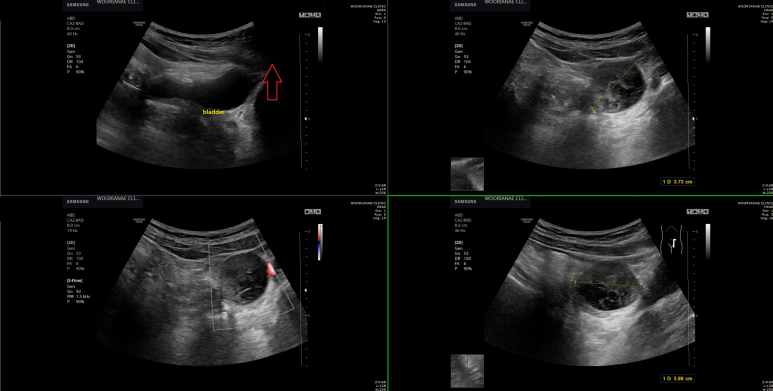

구토 후 지속되는 소화불량, 우연히 발견된 왼쪽 난소 종괴 의증, 소장 종괴? 가능성은?

50대 중반 여자 10여일전 구토증상으로 2차병원 응급실 방문 이후 메스껍고 답답한 증상으로 검진 및 내시경 위해 내원 내시경은 화생성위염 이외에 특이소견 없었으며 초음파도 간의 낭종 이외에 특이소견 없었으나 하복부 관찰시 우연히 발견된 종괴가...